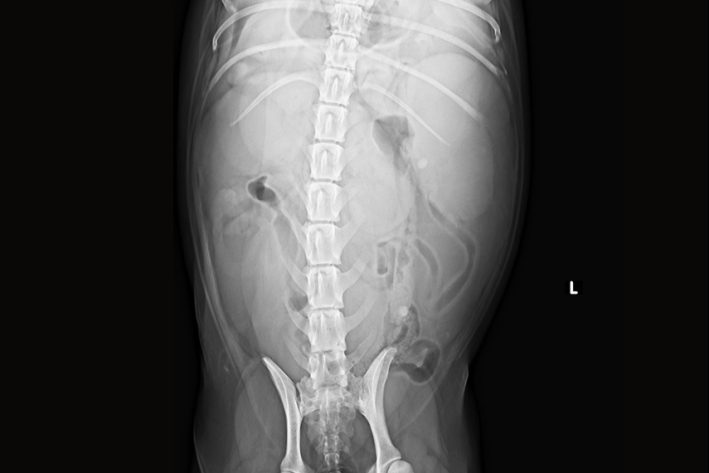

Pyometra: Röntgenbilder können bei der Diagnose hilfreich sein

Röntgenbilder können bei der Diagnose hilfreich sein

Pyometra Roentgen

Bei Tieren mit den oben angeführten Symptomen und Verdacht auf eine Pyometra wird eine komplette Abklärung angeraten. Diese beinhaltet die klinische Untersuchung und ein großes Blutbild inklusive Organwerte. Zur genaueren Lokalisation des Problems dient die Ultraschalluntersuchung der Bauchhöhle. Gegebenenfalls kann auch eine Röntgenuntersuchung durchgeführt werden. Der Vaginalausfluss kann unter dem Mikroskop genauer untersucht werden. Eine steril entnommene Gebärmutterflüssigkeit kann postoperativ für die bakteriologische Untersuchung eingeschickt werden.